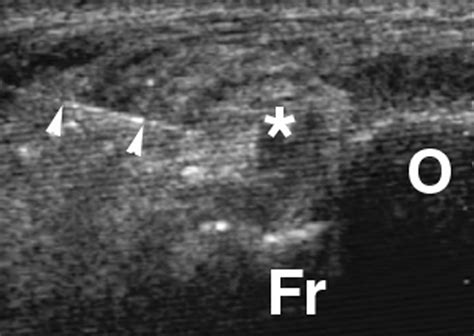

X-Ray Identifying bone spurs or an os trigonum.

MRI Scan Detecting soft tissue inflammation or ligament tears.

Diagnostic Injection Using anesthetic to confirm if the pain source is inside the joint.